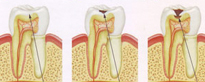

Endodontie

À Lakatos Dental vous bénéficierez des conseils d'experts aux problèmes relatifs à l’appareil dentaire maxillaire. Les œuvres fixes des couronnes ou ponts Le traitement du canal radiculaire est effectué quand la pulpe de la dent est infectée. Un dentiste ou un endodontiste enlève la pulpe du centre

Le traitement du canal radiculaire est effectué quand la pulpe de la dent est infectée. Un dentiste ou un endodontiste enlève la pulpe du centre  La prophylaxie dentaire est une méthode simple et peu coûteuse de prévenir la maladie dentaire mais également d'empêcher les complications